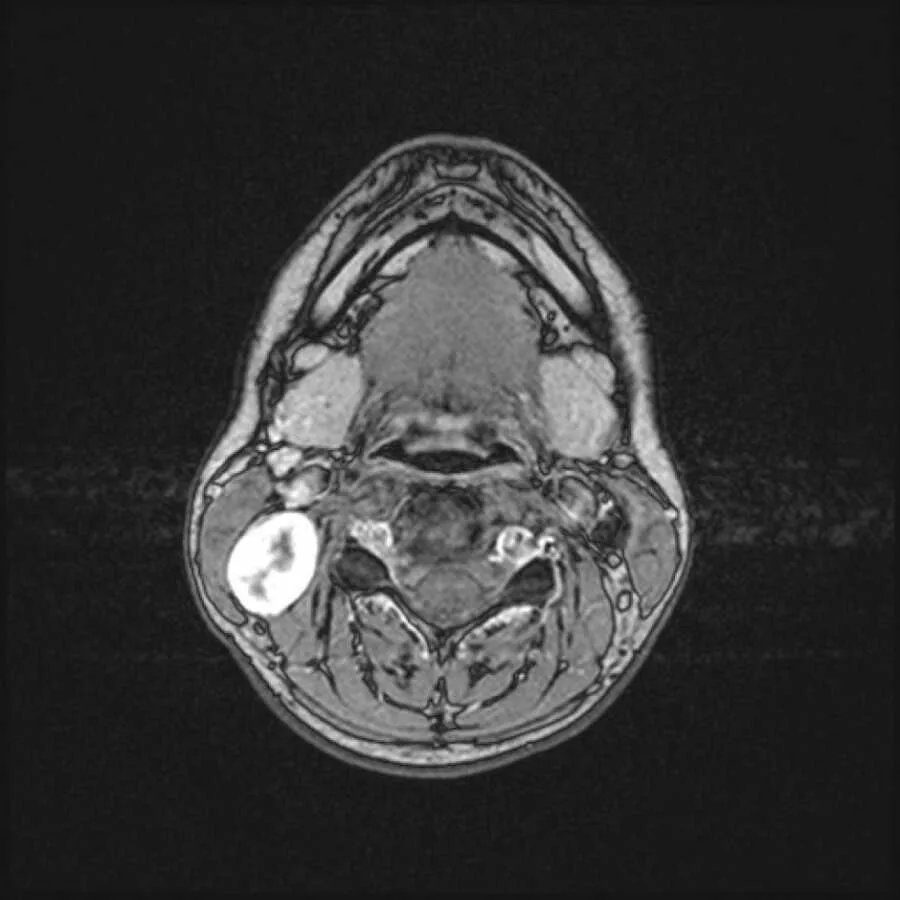

The diagnosis was a nerve sheath tumor, often benign, but tricky because it grows from the protective covering of nerves. That placement makes surgery hard; delay can press on nerves or the spinal cord. Since she had no significant symptoms yet, doctors suggested monitoring. So began years of MRIs, bills, and quiet fear. The tumor grew more than 20%, and although scans showed growth, they couldn’t say exactly which nerves were involved. Surgery became inevitable. Nerves could be irritated even if not cut; recovery could be slow or uncertain. She marked a date: December 29, 2021.

Surgery went better than expected. The tumor, a benign schwannoma, was removed with minimal damage. She had some numbness along her jaw, neck, and ear, like the fading buzz of dental anesthetic, but she could live with that. She exhaled for what felt like the first time in years. Then her video took off. Thousands, then millions, watched. Instead of judgment, she found kindness: prayers, messages from survivors, and notes from people finally making their doctor appointments.